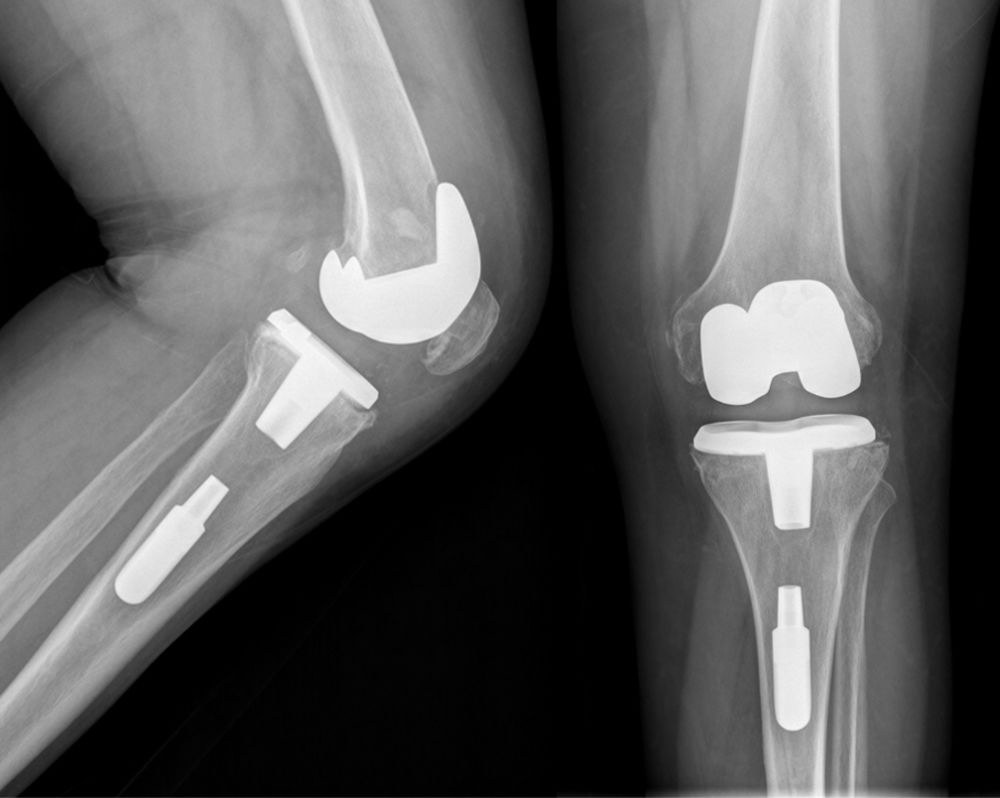

La cirugía de reemplazo de rodilla, también conocida como artroplastía de rodilla, consiste en sustituir las superficies articulares dañadas por componentes protésicos diseñados para aliviar el dolor y mejorar la función.

Es un procedimiento en el que se retiran las superficies dañadas del fémur, tibia y, en algunos casos, la rótula, para colocar implantes que permiten un movimiento más suave y menos doloroso.